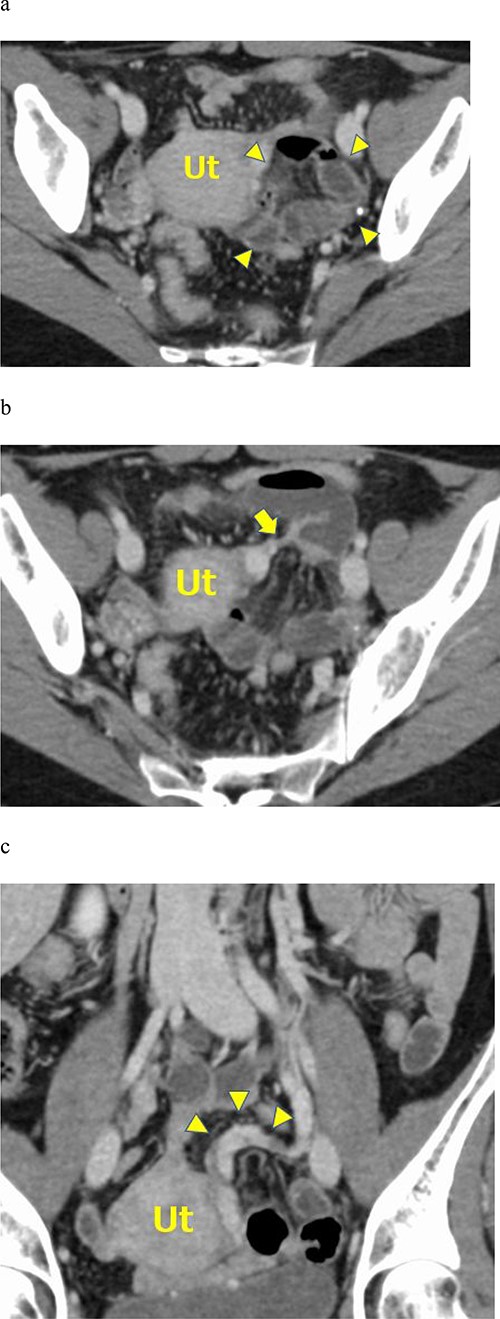

a. Contrast-enhanced axial CT showing fluid-filled dilated small bowel loops in the posterior pelvic cavity (arrowheads). The small bowel loops compressed the uterus on the right side. b. Contrast-enhanced axial CT showing mesenteric vessels converging around the uterus (arrow). c. Contrast-enhanced coronal CT images showing the left ovarian venous dilatation and tortuousness (arrowheads).

An abdominal X-ray examination revealed no niveau formation. Abdominal contrast-enhanced computed tomography (CT) using a 320-row multidetector CT (MDCT) scanner (Aquilion ONE, Canon, Japan) was performed. The contrast-enhanced abdominal CT showed a cluster of dilated small bowel loops on the left side of the pelvic cavity and bowel loops compressing the uterus on the right side of the pelvis (Fig. 1a). The CT scan showed mesenteric vessels converging around the uterus (Fig. 1b). A small amount of ascites was found at Douglas’ fossa. Contrast-enhanced coronal CT images showed left ovarian venous dilatation and tortuousness (Fig. 1c). Enhancement of the wall of the small bowel loops was not decreased, indicating the absence of bowel ischemia.